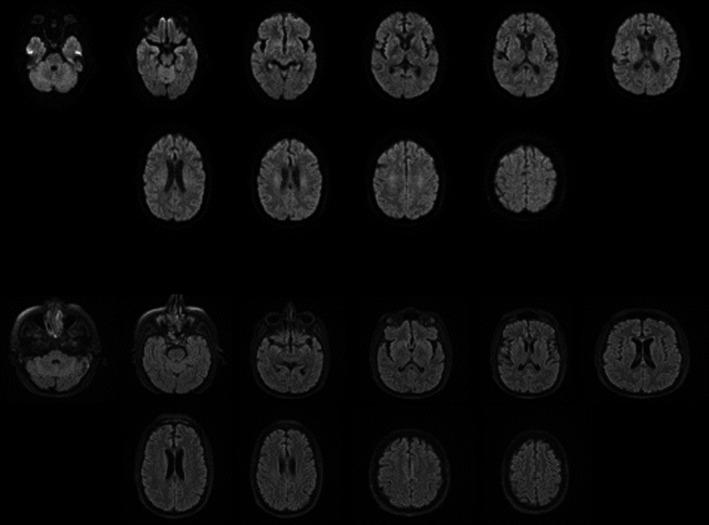

A case report of toxic leukoencephalopathy induced by metronidazole in a woman with surgical site infection.

Metronidazole may rarely cause encephalopathy and neuropathy. In this study, we report a 30-year-old post-partum, ex-addicted female with leukoencephalopathy due to metronidazole.

甲硝唑极少会引发脑病和神经病变。在本研究中,我们报告了一名30岁的产后、曾有药物成瘾史的女性,因甲硝唑导致白质脑病。